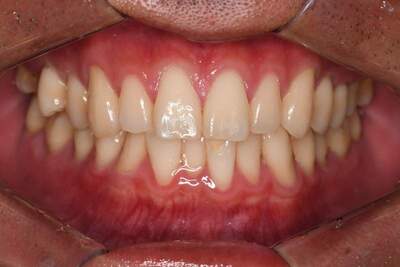

オフィスホワイトニング症例

治療前

治療後

主訴 歯を白くしたい

治療

内容

オフィスホワイトニング5回

方針

オフィスホワイトニング

期間

1ヶ月

費用 合計16,500円

オフィスホワイトニング5回 16,500円

(2022年7月現在)

リスク

副作用

知覚過敏が起こる・ホワイトスポット出現の可能性があります。 詰め物・被せ物は白くなりません。

ホワイトニングの効果は永久的ではなく徐々に色戻りします。

担当

者所見

短期間で白さが得られたと患者さまも満足されていました。白さのキープの為にホームホワイトニングも行う予定です。